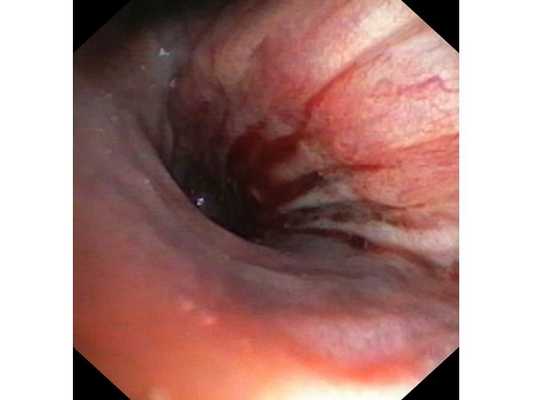

Первым этапом пациенту была проведена фибробронхоскопия, по данным которой выявлено, что устье нижнедолевого бронха слева сужено за счёт подслизистого и перибронхиального распространения опухоли.

Выполнена многократная биопсия из устья нижнедолевого бронха слева. По данным гистологического исследования материала эндоскопической биопсии верифицирован диагноз немелкоклеточного рака лёгкого.